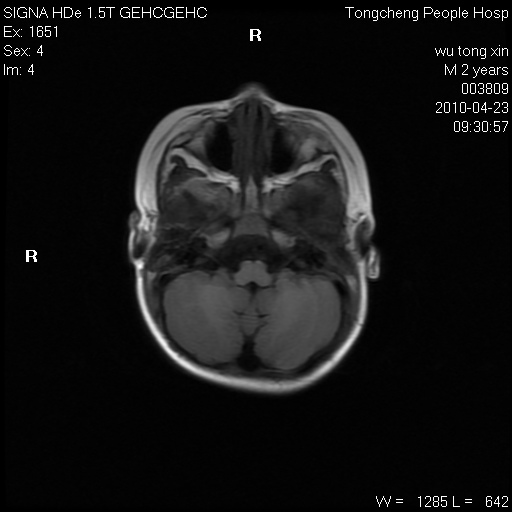

以下是引用赵物学在2010-4-25 12:43:00的发言:[br]巨脑回[br]侧脑室后角低密度影考虑hie或肾上腺脑白质营养不良?[br][br][本贴已被 赵物学 于 2010-4-25 12:51:28 修改过]

以下是引用gaoxiao在2010-4-25 16:54:00的发言:[br]巨脑回畸形。脑白质髓鞘化不良

以下是引用pujunzhi在2010-4-25 21:35:00的发言:[br]考虑 1双侧大脑皮质发育不良 2轻度脑积水 3双侧脑室后角旁片状长t1长t2信号,需继续观察,因为正常小儿此处脑白质的髓鞘化时间可以延迟到4-6岁,才显示正常。